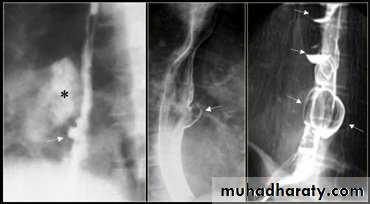

On the far left a traction diverticulum (arrow) due to hilar granulomatous disease. Calcified adenopathy (asterisk). In the middle a pulsion diverticulum (arrow) due to high intra luminal pressure.On the right multiple pulsion diverticula (arrows)